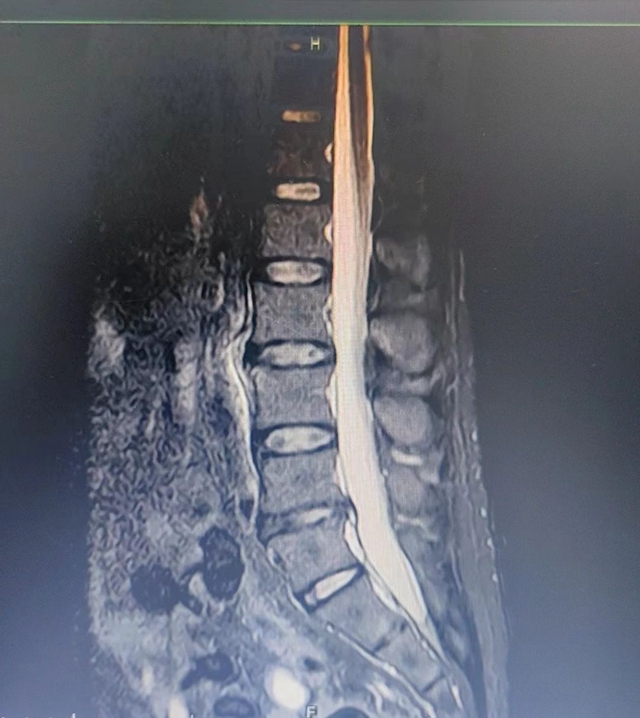

26岁的小王在一次外伤后出现了剧烈的腰痛和下肢放射痛,卧床休息、自行服药无效后到西南医科大学附属中医医院骨伤科脊柱·肿瘤二组,确诊为腰椎间盘突出症。

鉴于小王较年轻,且相关检查结果提示间盘突出节段稳定性良好,于是骨伤科脊柱·肿瘤二组专家团队决定为其实施单侧双通道内镜(UBE)下髓核摘除+纤维环缝合术。通过摘除髓核,解除神经压迫,缓解临床症状,并通过缝合纤维环破口,最大限度地保留椎间盘正常功能,降低新发突出风险。术后,小王即刻感觉腰痛及下肢疼痛有明显改善,配合中西医结合治疗,未见复发。